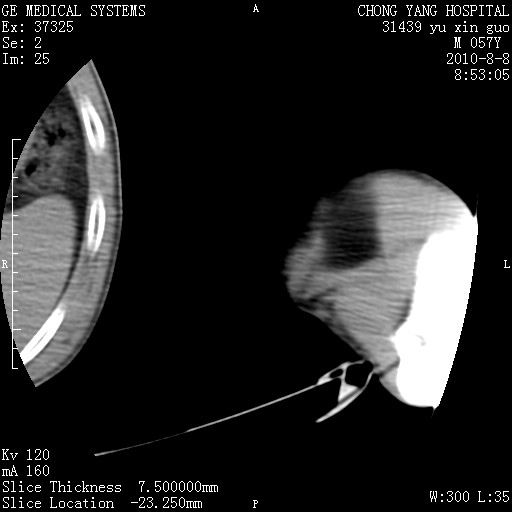

标题: CT28267:M57Y 上臂包块8年余。 [打印本页]

标题: CT28267:M57Y 上臂包块8年余。

包膜光滑、完整的脂肪密度肿块,支持脂肪瘤。

脂肪瘤。有ct值?